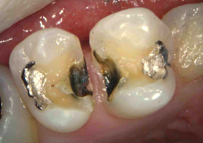

銀歯の除去後(むし歯が広がっています)、むし歯の除去と神経の保護